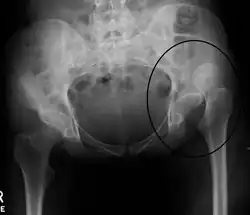

X-ray showing a joint dislocation of the left hip.

Dislocation of the left hip, secondary to developmental hip dysplasia. Closed arrow marks the acetabulum, open arrow the femoral head.